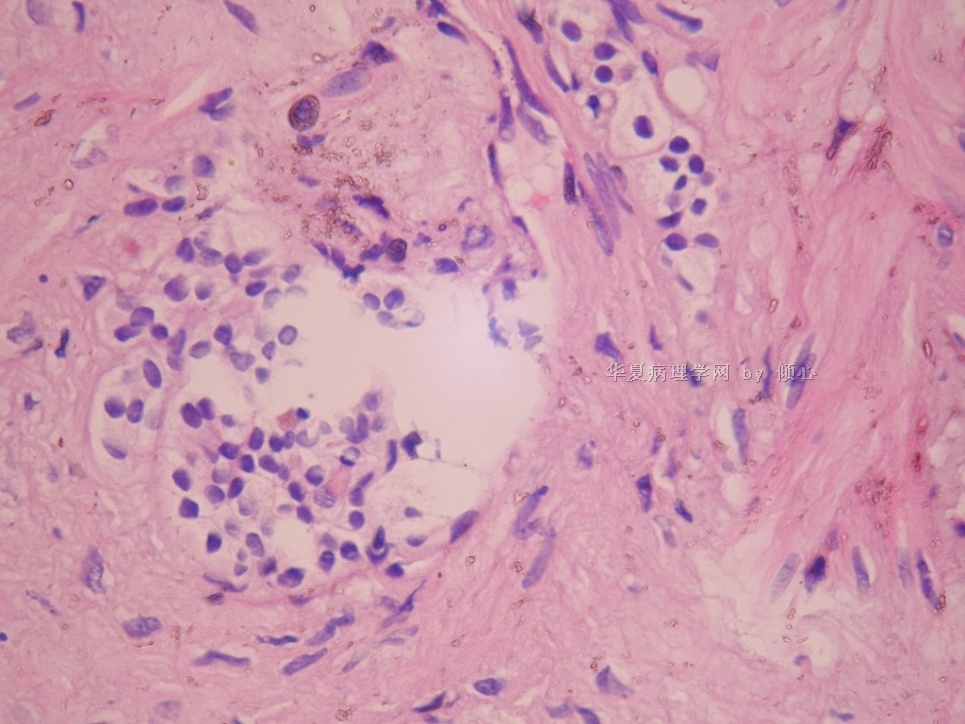

本帖最后由 于 2010-05-26 20:13:00 编辑  在左肾上极内见囊肿 ,这些透亮细胞在囊壁内。

可是,这是比较典型的肾上腺皮质细胞,不大像肾透明细胞癌的细胞。与之鉴别还是有必要的。需做IHC标记。

IHC广谱CK阳性,vimentin,RCC,CD10,CD68均阴性。

以下的图像是CK,取下的组织并不多,很少量的透亮细胞位于纤维性的囊壁内。需要鉴别的是残留的肾小管和囊性肾细胞癌。

囊壁无被覆透明细胞,纤维内的细胞巢有基底膜样物围绕,vimentin阴性,提示为萎缩的肾小管。冰冻时除非见到明显的被覆透明细胞,反之则请泌尿医师等石蜡。